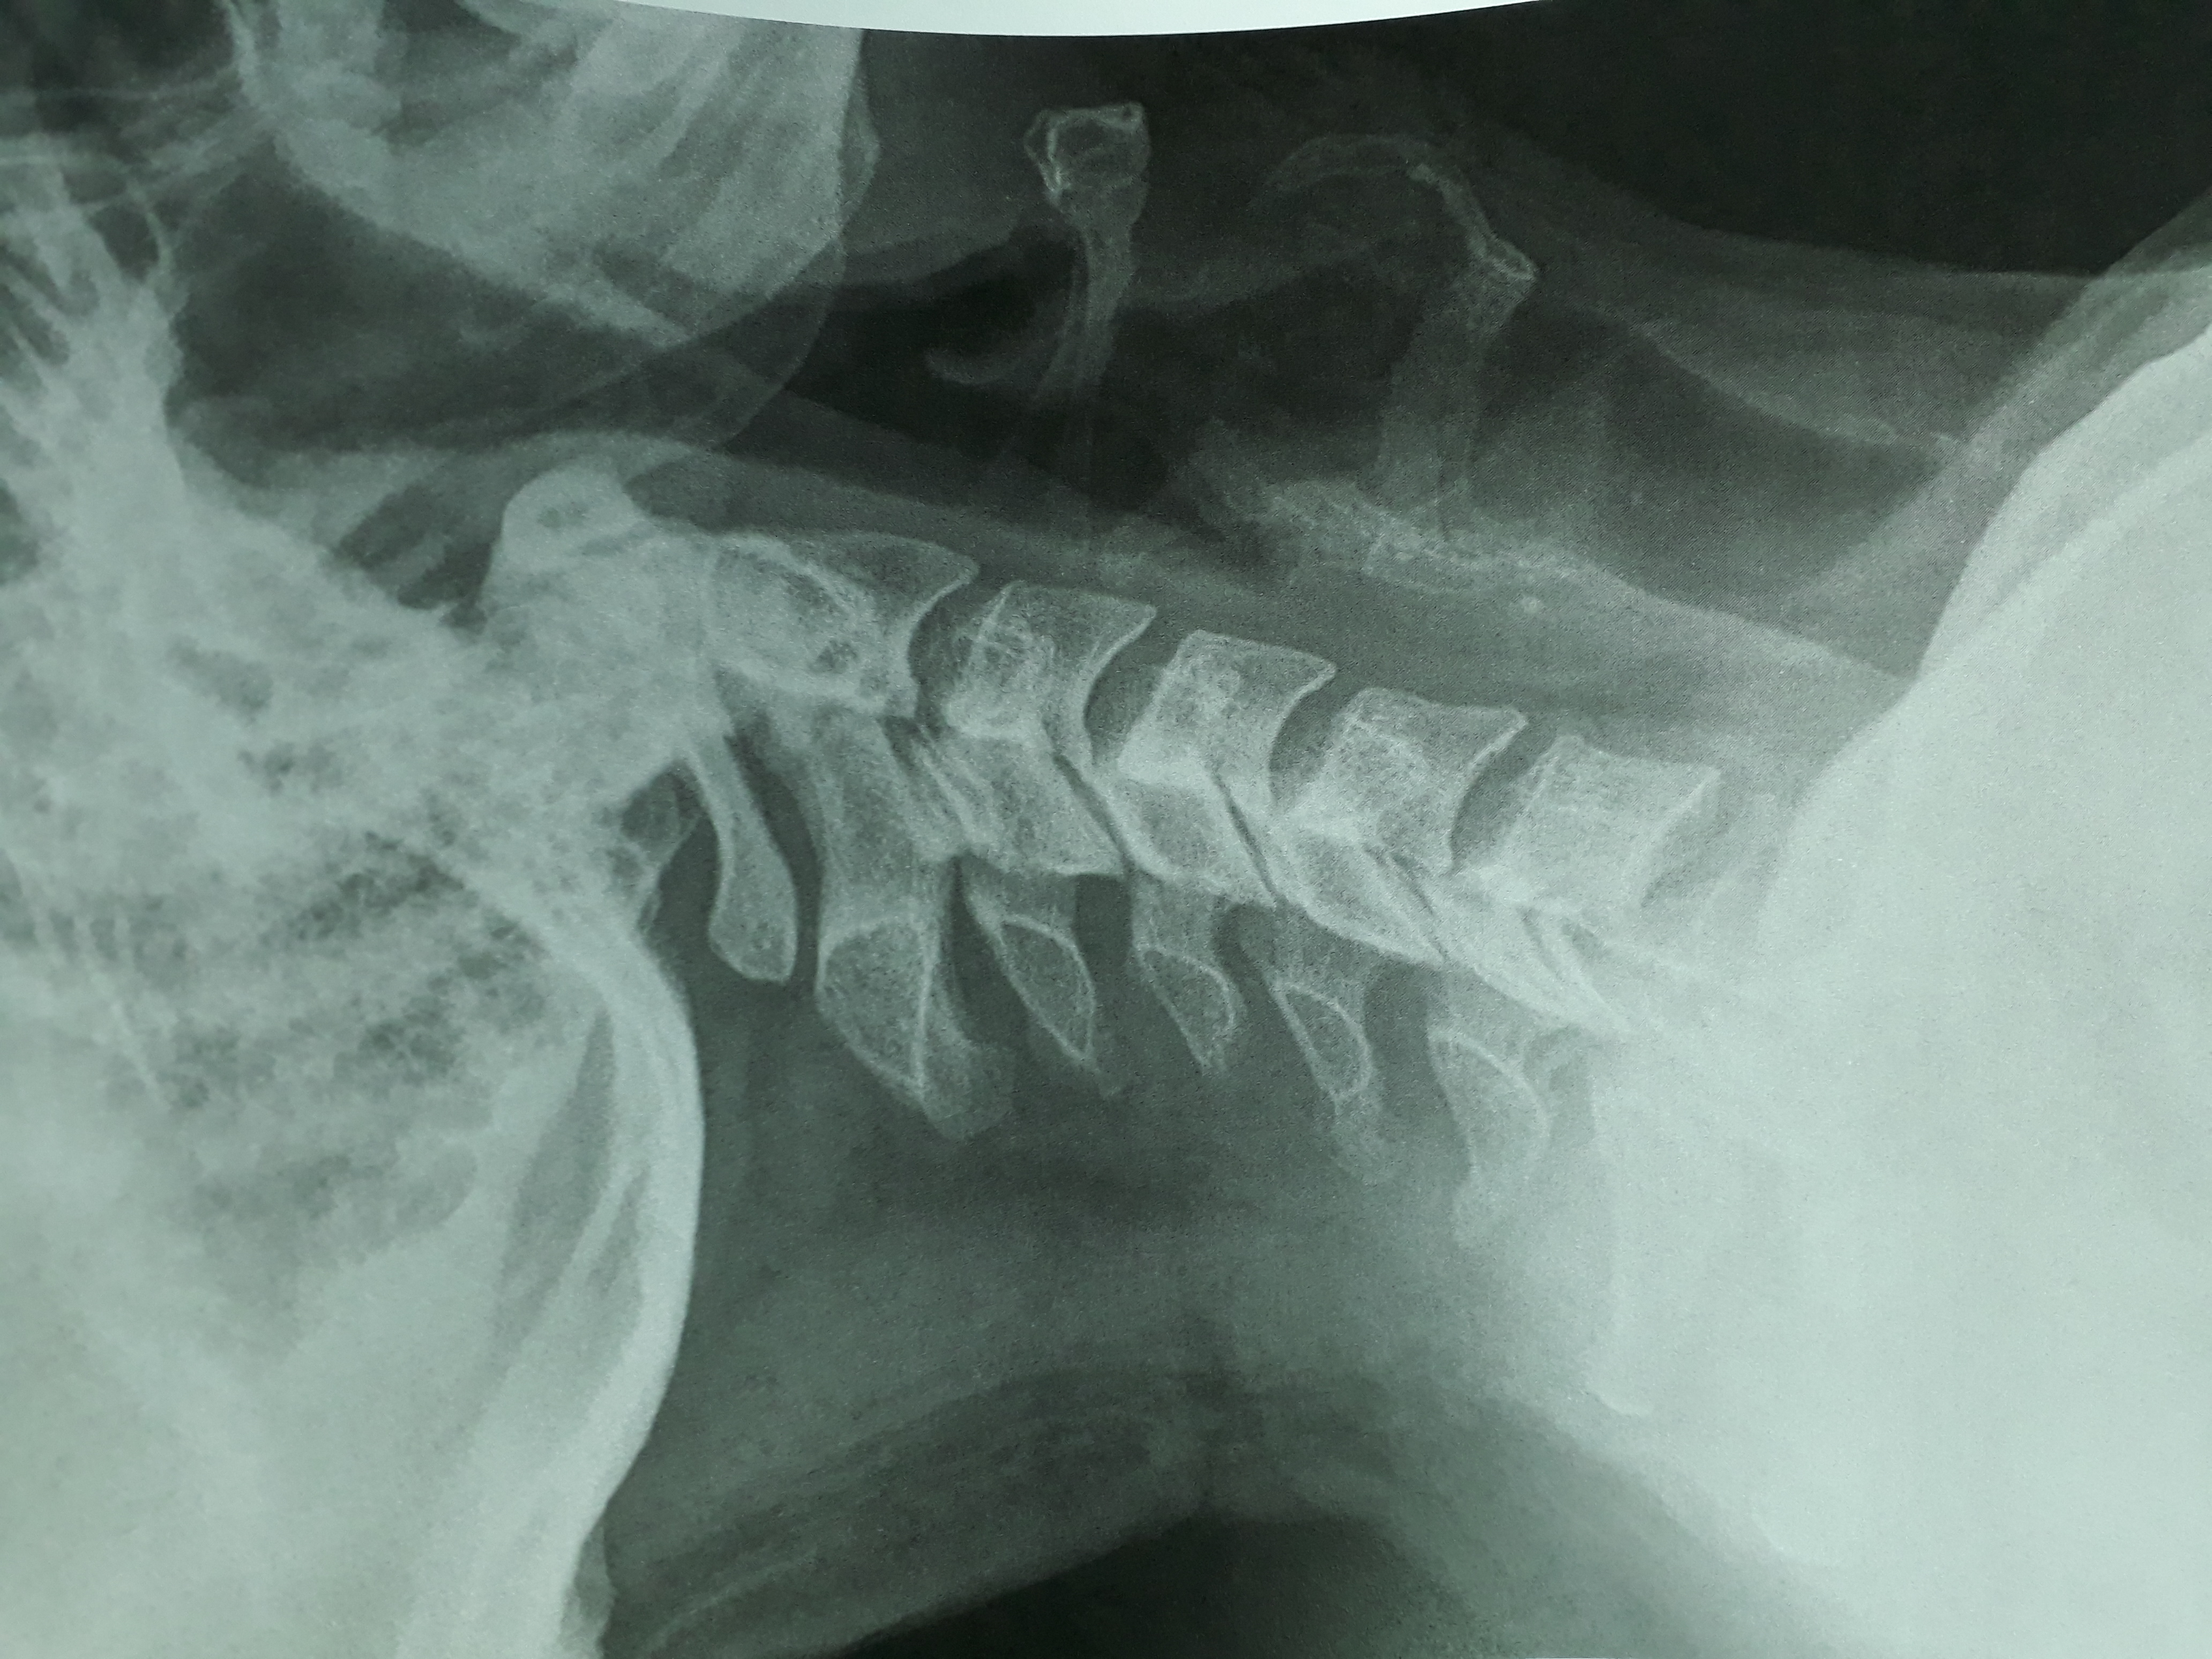

ich schicke mal ein Bild vom Röntgen. Ich bin der Meinung das der Abstand Dens-Atlas total unterschiedlich ist und es doppelt so grosse Abweichungen gibt.

Das lässt sich so etwas schwierig beurteilen da es nur zweidimensional ist, an einem Körper sind auch nur wenige Strukturen wirklich gerade beziehungsweise gleichmäßig, am einfachsten ist es die Stellung mal abtasten zu lassen…

Dens scheint ziemlich zentriert zu sein. Was auffällig ist, ist die HWS-Steilstellung.

kann diese Steilstellung der HWS auch mit dem Atlas zusammenhängen?

Mich irritiert der Abstand zwischen atlas-dens ( links) zu atlas-dens ( rechts)

Dens ist ok, ist nicht das Problem.